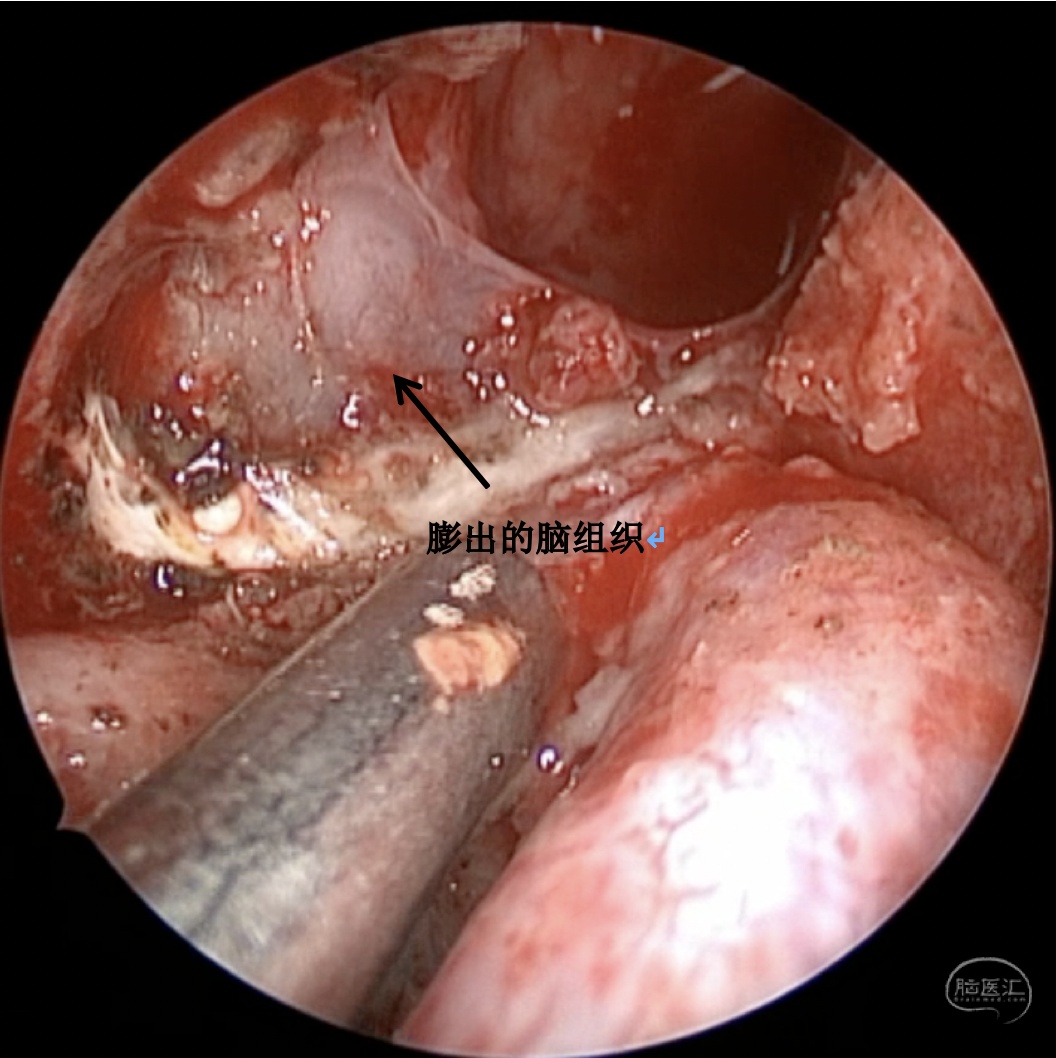

诊断:右侧蝶窦外侧隐窝脑膜脑膨出伴脑脊液漏。

病因分析:患者蝶窦过度气化,一直延伸至翼突,形成蝶窦外侧隐窝,造成中颅窝底出现薄弱区。患者第一次手术前因为松果体肿瘤,造成严重脑积水,颅内压明显增高,促使脑膜脑组织自颅底薄弱区疝出。但第一次手术术前并无脑脊液漏,而术后才出现脑脊液漏,可能的原因是:术前脑积水,造成颅内压较高,增高的颅内压一方面促使脑膜脑膨出,另一方面也迫使脑组织堵塞住了漏口,因而未出现脑脊液漏,手术后肿瘤全切除,脑积水缓解,颅内压下降,使得脑组织的堵塞漏口的作用下降,因此反而出现了脑脊液漏。

手术方案:内镜经鼻经翼突入路

术中情况: